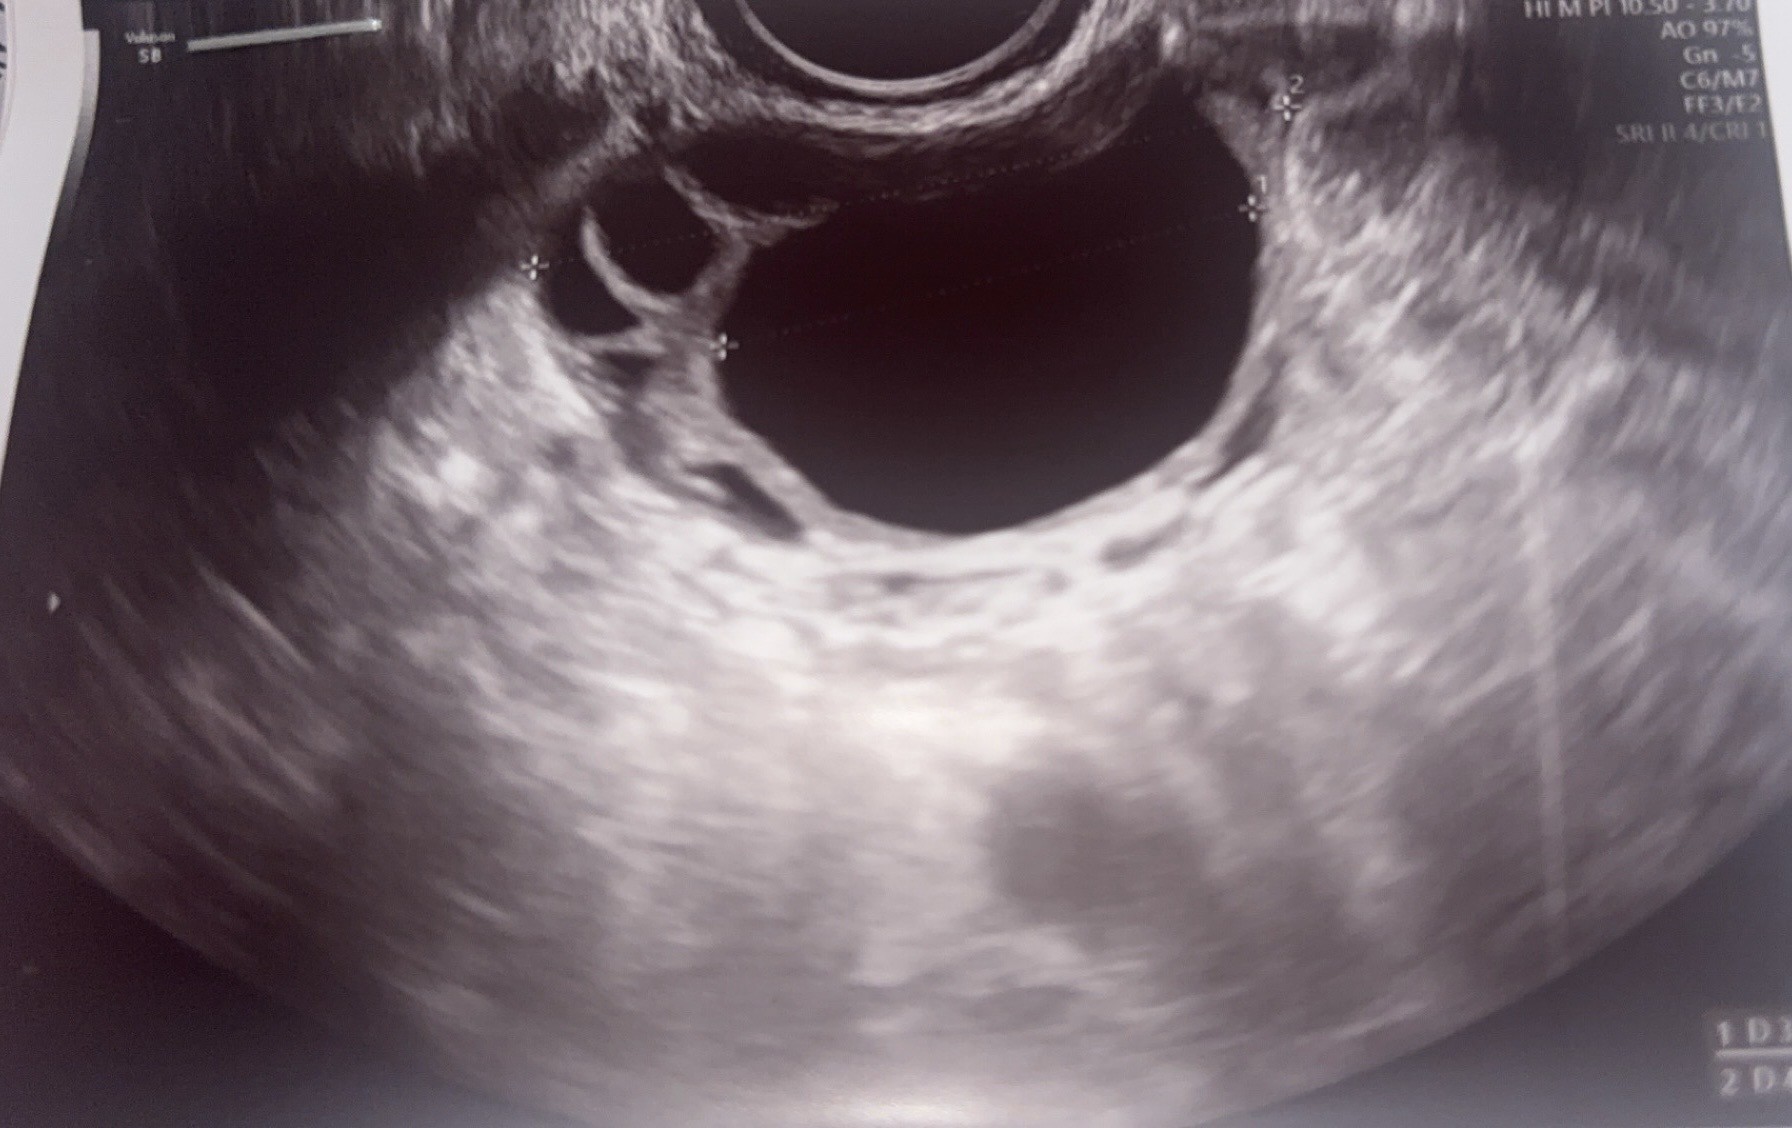

USG- czy widoczny pęcherzyk owulacyjny?

Może zna się któraś z Was, i powie mi czy widzicie na tych zdjęciach USG pęcherzyk owulacyjny?

Na jednym jajniku mam torbiel, ale ginekolog nie kazała się martwić bo jestem po poronieniu.

Endometrium mam 8,3 mm.